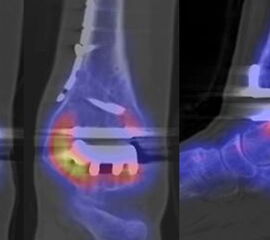

SPECT/CT zur Beurteilung von Endoprothesen

Weltweit nimmt die Prävalenz von Sprunggelenk-Prothesen durch Verbesserungen der Implantate und chirurgischen Techniken zu. Trotzdem berichtet ein signifikanter Anteil von Patienten über persistierende Beschwerden nach Prothesen-Implantation, sodass in der Literatur über Revisionsraten in bis zu 39 % der Fälle berichtet wird 5051. Die Ermittlung der Schmerzquelle mit den konventionellen bildgebenden Verfahren (Röntgen, CT, MRT (auch mit Metall-Artefakt-Reduktion)) ist begrenzt, so dass hier die SPECT/CT die Aussagekraft ähnlich wie bei der Beurteilung anderer Prothesen (z. B. Knie und Hüfte) signifikant erhöht. Verschiedenste Fragestellungen müssen bei der Evaluation einer schmerzhaften Sprunggelenk-Prothese beantwortet werden: Achsenstellung, Prothesenlage, Impingement, Lockerung, Senkung von Prothesenkomponenten, Frakturen, Zysten, Osteolysen, Anschlussarthrosen, Infektionen, Nervenschäden, CRPS, Materialunverträglichkeiten.

Zur Zuordnung von Mehrspeicherungen und morphologischen Veränderungen im Bereich von Prothesen eignen sich folgende Kriterien 51:

• Flächiger starker Fokus am Prothesen-Knochen-Interface → V. a. Lockerung

• Fokus medial oder lateral am Prothesen-Knochen-Interface → V. a. fokaler biomechanischer Stress aufgrund von Fehlstellung der Prothese oder des Rückfußes

• Fokus medial oder lateral im Gelenkabschnitt / Zone zwischen Talus und den Malleolen → Ausdruck eines Impingement

• Im CT zart randsklerosierte rundliche Osteolyse(n) am Prothesen-Knochen-Interface mit metabolischem Fokus → V. a. symptomatische Zyste

• Fokale oder flächige Mehranreicherungen in angrenzenden Gelenken in Verbindung mit arthrotischen Veränderungen im CT → V. a. symptomatische Arthrose

Beispiele für SPECT/CT-Untersuchungen nach OSG-TEP sind in den Abbildungen 6.1. bis 6.3. abgebildet.

Gurbani et al. evaluierten 37 Patienten mit schmerzhaften Sprunggelenkprothesen mit SPECT/CT und korrelierten die Ergebnisse mit klinischen und intraoperativen Befunden. Die SPECT/CT-Ergebnisse korrelierten zu 89,2 % (33/37 Pat.) mit der definitiven Diagnose. 28 Patienten wurden operativ revidiert und der Vergleich der SPECT/CT-Befunde mit den intraoperativen ergab eine Übereinstimmung von 92,9 % (26/28 Pat.). Die SPECT/CT identifizierte in den meisten Fällen aseptische Lockerungen (12/33 Pat.) und Impingement (11/33 Pat.). Seltenere Diagnosen waren Fehlstellungen (4/33 Pat.), Zystenbildungen (2/33 Pat.), subtalare Arthrosen (2/33 Pat.) und Infektionen (2/33 Pat.) 51.